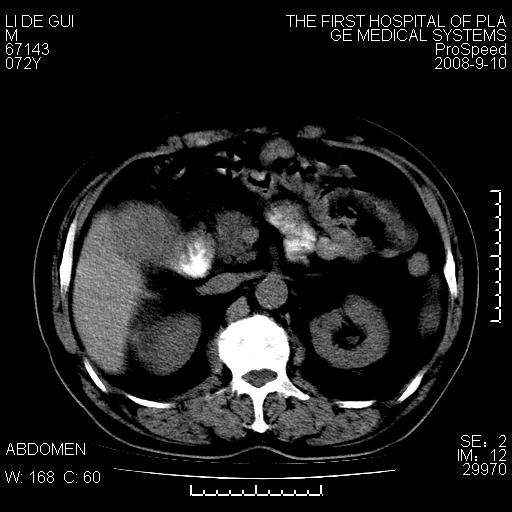

标题: CT17988:腹部肿块两年,肿块大小无变化,患者无不适,自我 [打印本页]

标题: CT17988:腹部肿块两年,肿块大小无变化,患者无不适,自我

考虑淋巴瘤!

不可思议!两年无变化无症状?建议详查!

胆囊占位性病变(黄色肉芽肿性胆囊炎?)。

考虑-----胆囊血肿机化或胆囊癌或腺肌增生症------增强

胆囊占位性病变,增强。

十二指肠的间质瘤